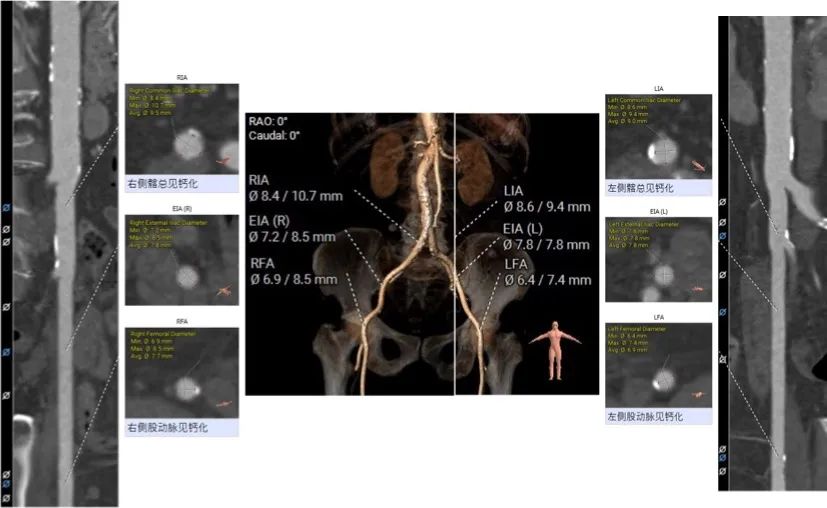

股动脉入路:

该患者瓣环最小径22.4mm,且瓣叶重度钙化,此外左无冠窦之间有一处柱状钙化延伸至LVOT,决定术中用20mm球囊预扩,评估冠脉风险和指导瓣膜选型。此外,患者双侧瓣叶长度均大于冠脉高度,且左冠团状钙化,冠脉遮挡高危,拟在TAVR前行左冠支架保护。

主入路:右侧股动脉

辅入路:左侧股动脉